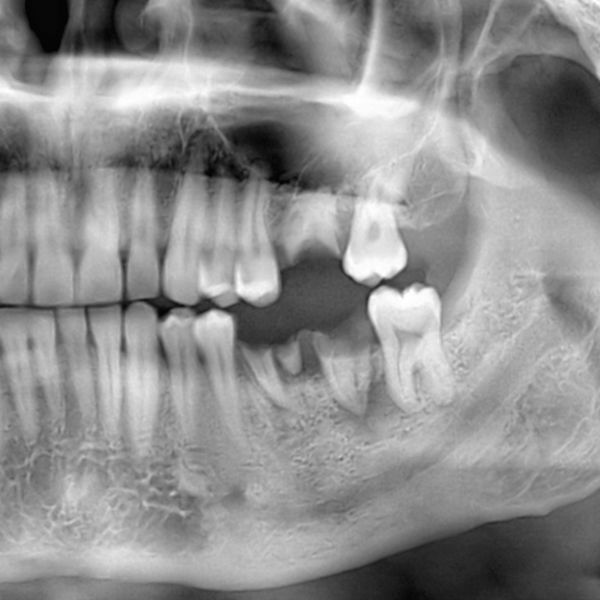

Studies have shown that within six months following the extraction of a tooth, approximately half of the bony alveolar ridge height and width are lost due to the resorption of the remaining bone. This can create problems, because the bony ridge may be needed later to support an implant or another type of dental prosthesis. Fortunately, there is a way to prevent this bone loss from occurring. This treatment is called socket preservation. Dr. Jon Marc Van Slate who practices dentistry in Houston, TX, knows how important socket preservation can be for future restorative treatments, and he wants his patients to understand more about it, as well.

This is the technique for placing bone grafting material at the site of a tooth extraction. By so doing, the alveolar ridge, or ridge of bone that exists around the extraction site, can be better preserved. Socket preservation serves another purpose besides helping maintain the bone structure that may be needed later. It also helps prevent a painful complication of tooth extraction that occasionally occurs, called dry socket. The grafting material acts to keep the blood clot in the healing socket intact, preventing recurrent problems. If it is lost, a dry socket can occur.

Socket Preservation is a relatively simple procedure the dentist can readily accomplish in conjunction with the extraction. After the tooth is extracted, the dentist carefully places the grafting material in and around the socket before suturing the soft tissue back to place, covering the opening to the socket. Depending on the circumstances, a membrane—either resorbable or non-resorbable—may be positioned over the grafting material but under the gum tissue. Its purpose is to help stabilize the grafting material and encourage the growth of new bone. The type of grafting material the dentist chooses to use can be derived from animal bone, human bone, or synthetic materials. Regardless of the type, all are highly purified, safe, and proven to be effective.